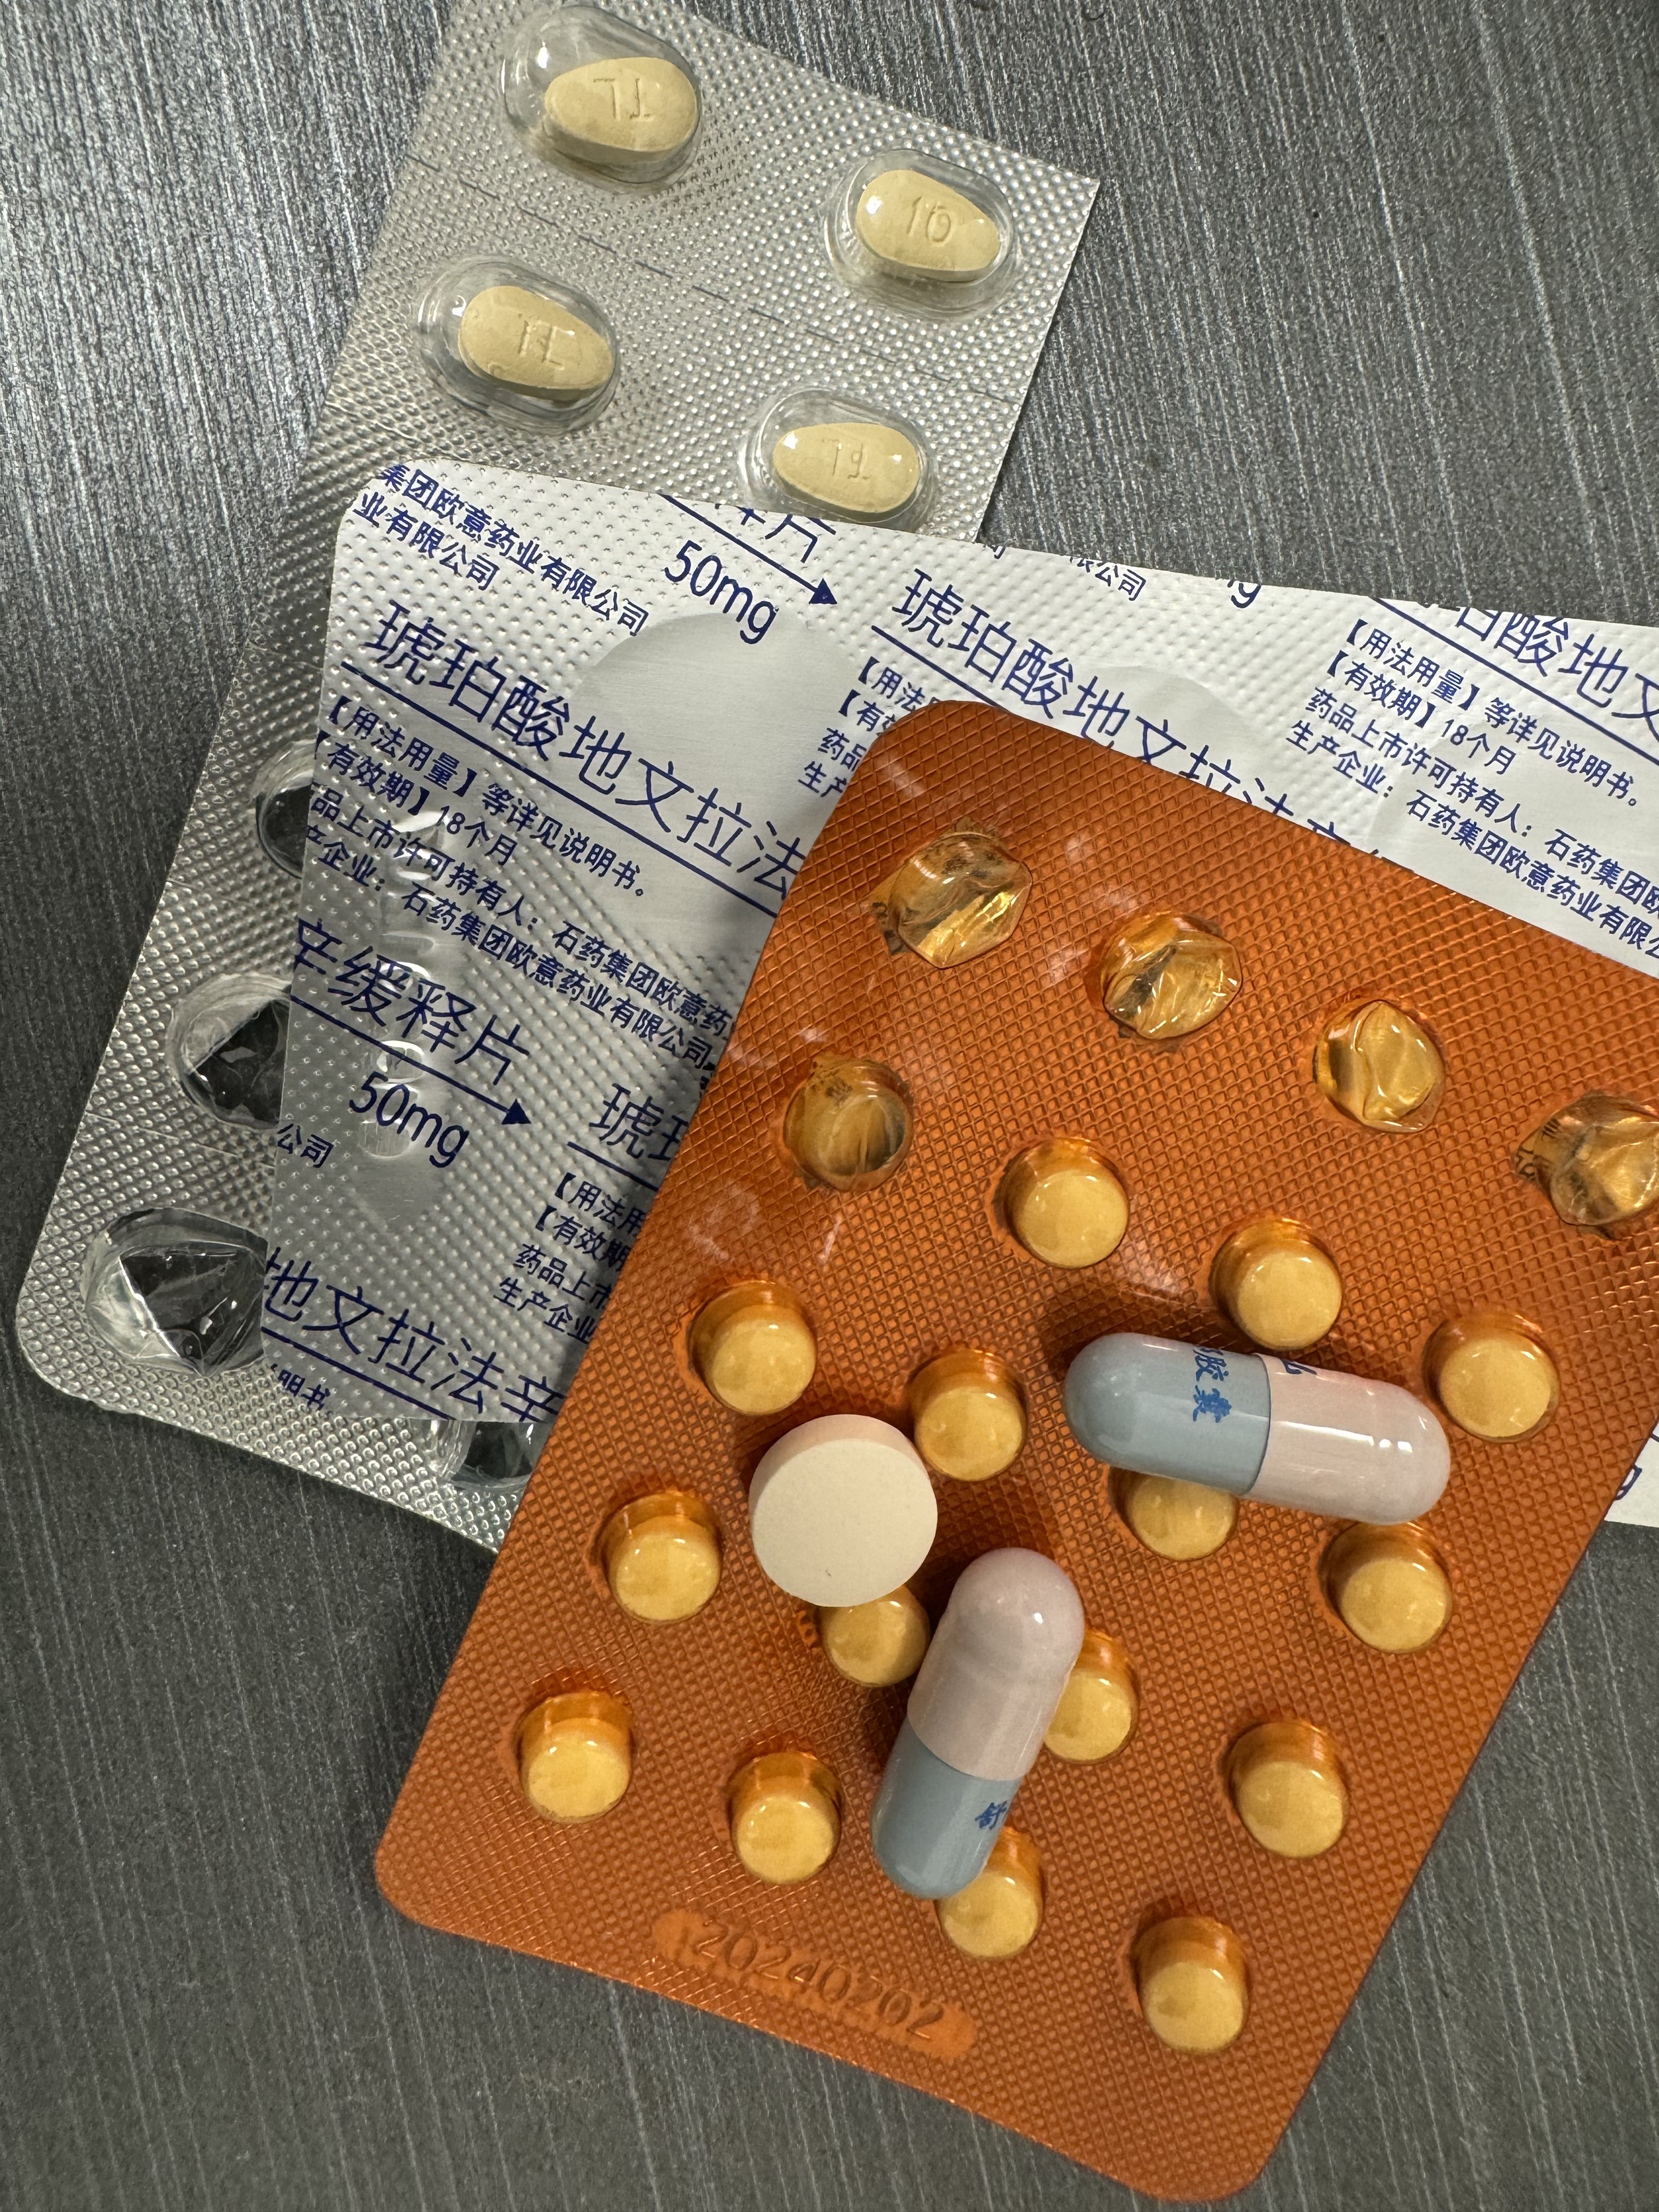

关于后藤提到过的“反解离”

首先,从定义上讲,“反解离(anti-dissociative)”并不是一个标准的医学术语或者广泛认同的药理学分类。在正规资料,比如医学文献、维基百科、精神药理学教科书中,目前并没有“反解离药物”这个正式概念。

看上去像是为了描述某类特定效应而创造的术语(可能是nmda受体活性增强),用来对抗因NMDA受体拮抗剂(比如氯胺酮、DXM、PCP等)引发的解离体验(dissociation)。

那么更常见的是将其归入认知增强剂(cognitive enhancers),特别是改善认知连接性(connectivity)和现实感知(reality testing)的类型。

但其实在药理学上,单纯用“受体激动剂”来逆转“受体拮抗剂”的效应,有时会导致过度激活。

对于NMDA受体而言,过强的NMDA活化本身就与兴奋性毒性(excitotoxicity)和精神病样症状(psychotomimetic effects)有关,比如谷氨酸风暴可以引发严重的焦虑、妄想、乃至癫痫。

也就是说,简单地“激动-解除拮抗”在中枢神经系统是很危险的做法,尤其是对于易感个体(如有精神分裂素质的人)。

科学的处理方式一般是通过更细致的调节,比如微调NMDA/AMPA平衡、调节其他辅助途径(如GABA、5-HT、mGluR受体),而不是简单粗暴地用“NMDA增强剂”去顶回去。

而临床处理药物中毒中,其实医生更常用的做法是保守、支持性的治疗,比如补液,促进代谢,必要时镇静,以及监测生命体征防治并发症。

药物拮抗与受体激动之间,往往牵扯到的是复杂的适应性变化(receptor upregulation/downregulation),

不是简单的“给多一点刺激就能抵消”的关系

金刚烷胺会对神经系统造成长期/不可逆的影响

首先多巴胺系统

金刚烷胺作为多巴胺释放促进剂,在长期使用或过量下可能导致:

-DA系统适应性衰竭(Receptor downregulation)

-药源性多巴胺枯竭综合征:表现为认知退化、动机缺失(apathy)、情绪迟钝等。

NMDA

虽然金刚烷胺是弱NMDA拮抗剂,但长期使用可能导致:

-突触可塑性损伤(LTP/LTD受阻)

-情景记忆下降、学习能力减退

-焦虑、攻击行为升高

-神经元代谢负荷增加,增加兴奋毒性风险

金刚烷胺提高兴奋性毒性(NMDA活性失衡、多巴胺代谢紊乱),与致幻剂合用或交替用药会:

-加剧皮层-边缘系统的不稳定性(例如海马体、前额叶)

-增加精神病风险(psychosis risk)

-导致长期认知损伤与感知畸变的残留症状(HPPD-like states)

另外有导致神经适应性结构改变

动物研究提示,金刚烷胺长期使用可能导致:

-树突棘数量下降

-突触可塑性衰退

-神经炎症因子(如IL-6)升高,为不可逆脑损伤打下基础

2025-04-29 11:45:39 UTC

简版

金刚烷胺不但无法提供真正的致幻体验,反而会破坏大脑、干扰神经系统,带来无法逆转的损害。

短期风险:

-幻觉质量差、碎片化,常伴恐惧、迷惑、妄想

-谵妄状态(严重的意识混乱)

-焦虑、失眠、暴躁、攻击性升高

-心跳紊乱、口干、头晕、甚至癫痫发作

长期风险:

-损伤大脑中的多巴胺与谷氨酸系统

-学习能力下降、情绪变平淡、认知迟钝

-增加患上药源性精神障碍的风险